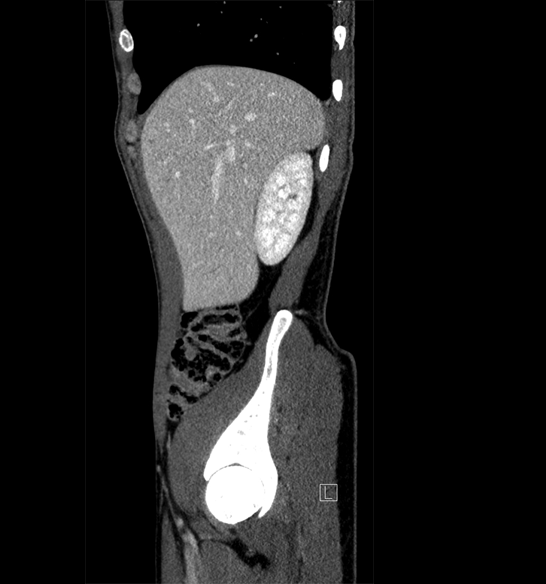

Body

Covers abdominal CT anatomy.